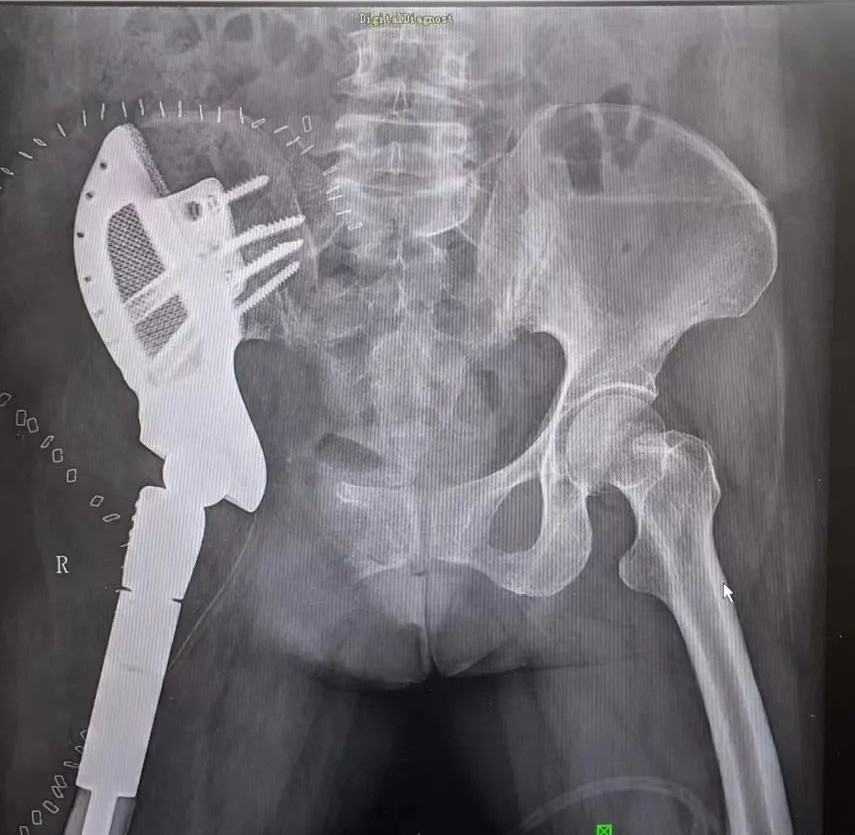

经过精心的准备,手术开始了,从早上八点多开始,到晚上七点多结束。从髂骨到股骨,从分离到截骨,张兵及其团队依靠精湛的手术技艺,经关节外完整切除瘤段病灶,终于将张阿姨体内的巨大肿瘤完整切除,并将3D打印制作的假体放置于其体内,最终手术圆满成功。

“患者的病灶范围很大,从盆骨向下生长侵袭股骨经过髋关节,直到骨盆,要想完全清除病灶,手术必须要在髋关节外进行,完整切除骨盆及股骨上段病灶,因为如果打开关节,肿瘤切碎后形成肿瘤细胞会脱落于体内,引起新一轮的复发。当时患者病灶已经突破骨皮质,侵及软组织常规的关节内切除无法达到肿瘤外科的手术切除边界要求,同时重建骨盆及股骨,所以手术难度相对还是挺大的。”谈起这场手术的难度,张兵到现在还记忆如新。切除只是手术的第一步,更重要的是要帮助患者精准地重建还原生理结构,保障其后的生活质量。“我们利用3D打印技术,为患者订制了两个个体化的髋关节假体,假体大小结构精确到毫米,使假体可与患者精准契合,最大化重建和恢复其身体的力学结构。”近几年来,张兵团队利用3D打印技术,帮助了无数患者恢复正常生活。

术后假体安置情况